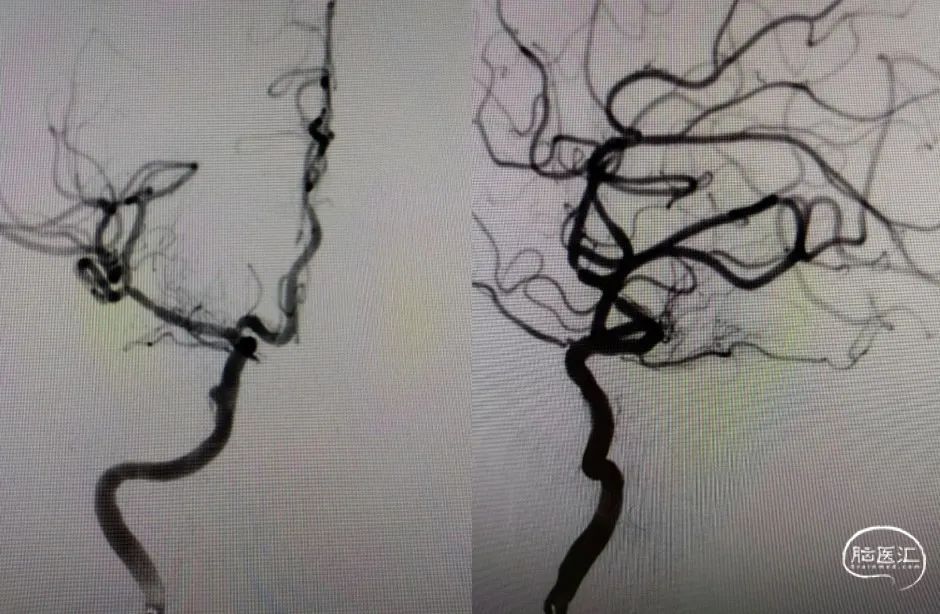

Guiding到位,导丝通过病变。

球囊通过病变。

球囊扩张过程。

扩张后造影。

支架通过病变。

支架释放。

术后影像及检查

术后正位造影。

术后侧位造影